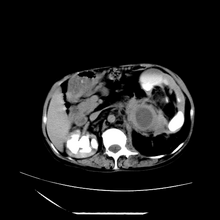

女性,41岁,发现左腹部包块3年,现行ct检查,检查前做过静脉肾盂造影。

左侧低密度区是脂肪密度,中间可见条索状软组织样密度影,现主要想知道左肾前下缘圆形软组织样密度影,内见低密度水样密度影,这是什么?

脾脏增大,左肾后方脂肪增多,脊柱前方脂肪增多,左肾窦脂肪增多,左肾变形,双肾积水以左侧为著,左肾内侧及上方见环形软组织肿物影,内部低密度区,考虑1盆腹腔/腹膜后及左肾窦脂肪增多症2左肾内侧病灶可能为左肾上腺病灶,可能为脂肪增多的原凶

1)考虑左肾替代性脂肪瘤病;不排除左肾错构瘤。2)双肾积水。

肾窦脂肪瘤病及肾替代性脂肪瘤病被认为是脂肪增殖程度不同的一种疾病。正常情况下肾窦内有少量脂肪组织充填,在某种情况下肾实质会发生萎缩,而以肾窦、肾门为中心脂肪或(和)纤维组织可出现增殖,当增殖局限在肾窦、肾门区时称为肾窦脂肪瘤,若同时部分或全部取代了萎缩破坏的肾实质时称为肾替代性脂肪瘤病。

发病机理有2种学说,大部分人认为是由于某些具有破坏性的肾脏疾病,如肾结石并感染、肾结核等造成肾破坏、萎缩,继发了大量的脂肪组织增殖;另一部分则认为肾脏慢性炎症可刺激脂肪组织的增殖,肾萎缩是继发的。

ct典型表现为以肾窦肾门为中心大量弥漫性脂肪积聚,鹿角状结石及萎缩的肾实质。合并肾周感染时,肾轮廓不清,周围有粘连性改变。

诊断rsl的必备条件是肾窦、肾门的脂肪组织增生和肾实质的萎缩,而且本例因为ivp后扫描不好判断有无肾结石但可能性较小;另外,占位效应显著,脾后缘都受压了,肾门以下肾实质残缺,支持肾脏错构瘤.